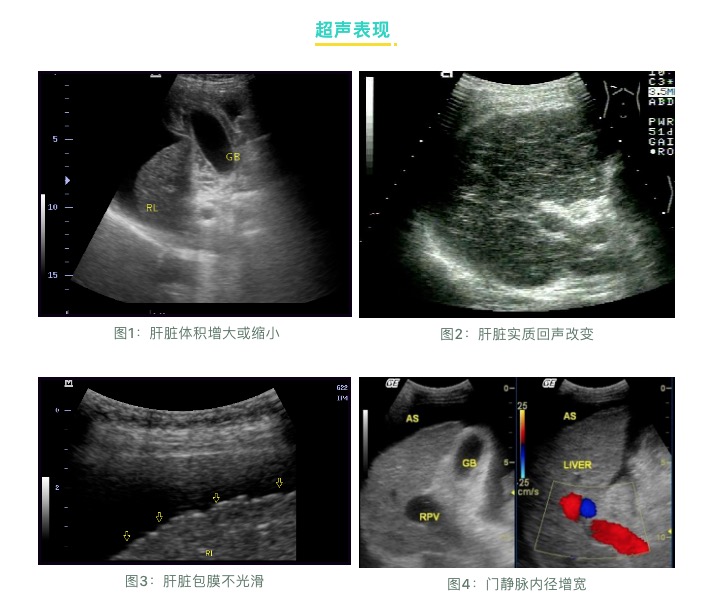

超聲檢查:

肝臟受病毒感染和發(fā)生炎癥后,就會(huì)造成肝臟內(nèi)部的結(jié)構(gòu)損傷,從局部的纖維化、結(jié)節(jié)性肝硬化到最后的全面硬化,超聲檢查是早期發(fā)現(xiàn)肝硬化的最直接指標(biāo)。